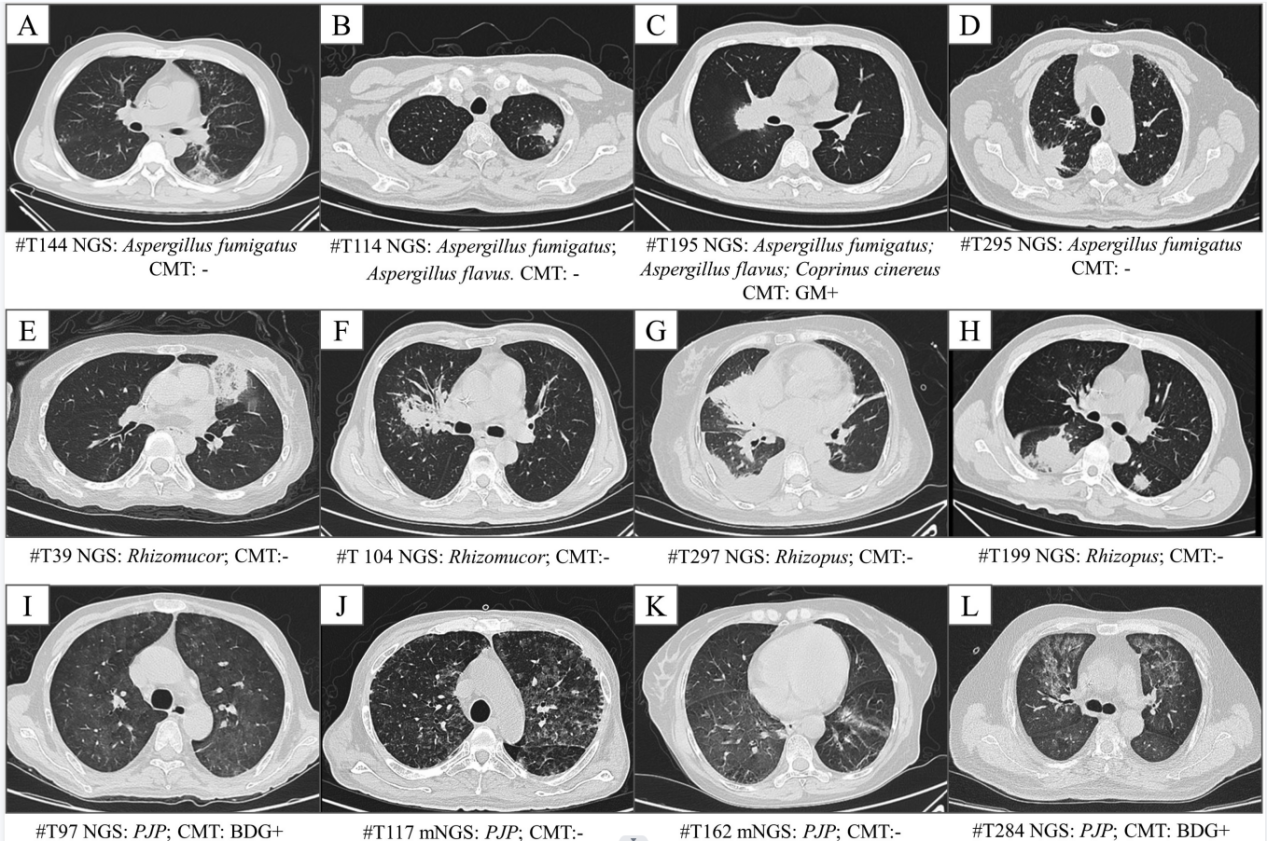

隨后,研究者對血液樣本病原mNGS檢測在疑似肺部真菌感染患者中的診斷價值進行分析。結果顯示,曲霉、毛霉、肺孢子菌這三種血液病患者肺部感染最常見的真菌病原,檢出率分別為14.2%、8.1%和5.0%。其中粒缺患者曲霉檢出率高于非粒缺患者,檢出曲霉的23名患者中,傳統微生物學檢測僅檢出10名患者。對檢出真菌的46名患者,臨床醫生對其半數以上進行了藥物調整,優化了抗真菌感染治療策略。